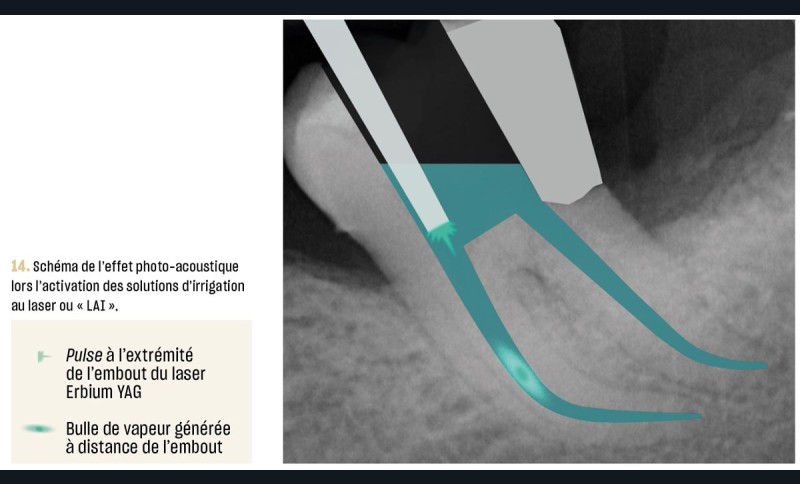

Les préparations « laser-assistées » (« laser-activated irrigation », LAI en anglais) au laser Erbium YAG s’inscrivent parfaitement dans les principes actuels de traitements conservateurs (fig. 13). Par rapport aux autres longueurs d’onde des lasers utilisés en odontologie, le laser Erbium YAG (2 940 nm) a l’absorption la plus élevée dans l’eau (de l’ordre de 98 %) et la plus minime dans l’hydroxyapatite. Cela veut dire que son action se fait au sein de la solution d’irrigation et non sur les tissus durs de la dent. Dans la solution irradiée, l’onde pénètre à une profondeur d’environ 1 µm, évitant ainsi la diffusion thermique au sein des parois radiculaires et des structures parodontales. C’est donc le laser de choix pour l’activation des solutions en endodontie.

Lors de préparations « laser-assistées », le nettoyage et la désinfection résultent de phénomènes photo-acoustiques, photomécaniques et photochimiques induits au sein de la solution aqueuse irradiée. Le principe physique réside dans la conversion de la lumière laser en chaleur. L’énergie du laser, émise sous forme de tirs (ou pulses en anglais), chauffe la solution et induit un phénomène d’ébullition qui génère l’expansion de bulles de vapeur d’eau (fig. 14). Certaines de ces bulles vont osciller dans le champ acoustique et générer des effets photo-acoustiques. D’autres bulles vont préférer grossir jusqu’à atteindre un volume maximum critique, au-delà duquel la pression interne devient inférieure à celle du liquide environnant. Une fois le tir laser interrompu, les bulles s’effondrent violemment sur elles-mêmes, produisant un collapsus à l’origine d’ondes de choc et de jets de liquide à grande vitesse : c’est le phénomène de cavitation [28] (fig. 15). L’absorption de la lumière émise par le laser Erbium YAG est si intense dans la solution que la vaporisation est immédiate et superficielle. En outre, la très brève durée du pulse (quelques centaines de microsecondes) évite les phénomènes de diffusion thermique.